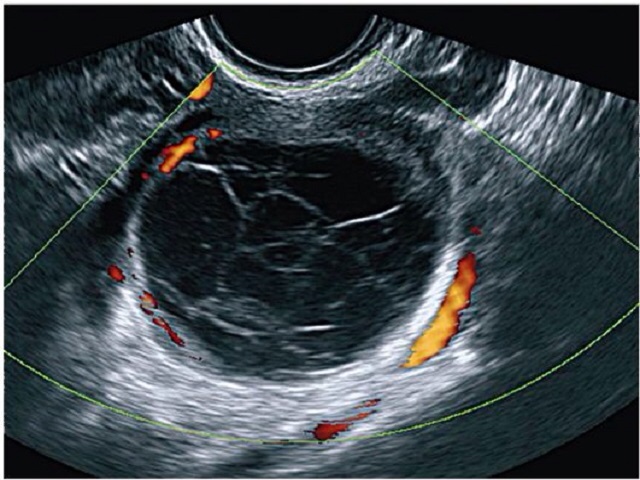

О полноценности желтого тела также нужно судить по характеристикам кровотока в артериях этого самого тела.

В сосудах нормального желтого тела снижение ИР в среднем до 0,44 отмечается уже на 2-й день после овуляции, причем этот показатель практически не меняется в течение первых 5 дней лютеиновой фазы. В лютеиновую фазу ИР ступенчато повышался в среднем до 0,47 и в дальнейшем постепенно увеличивался в среднем до 0,53 к концу лютеиновой фазы. А вот ИР выше 0,53 говорит о неполноценности лютеиновой фазы.